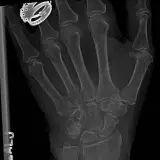

Over 2,100 interactive radiology cases, curated by radiologists for your level of training. Scroll, window, and view cases full screen — just like on PACS. Click linked findings in each writeup to jump straight to them on the image. Cases include sample reports, a focused discussion section, original illustrations, and videos.

Casos totalmente interativos com as ferramentas que você espera em um PACS — rolagem, ajuste de janela, zoom, movimentação, medidas, ROIs e modo de tela cheia.

Casos Interativos

Role, movimente, ajuste janela e amplie como em uma estação PACS do trabalho